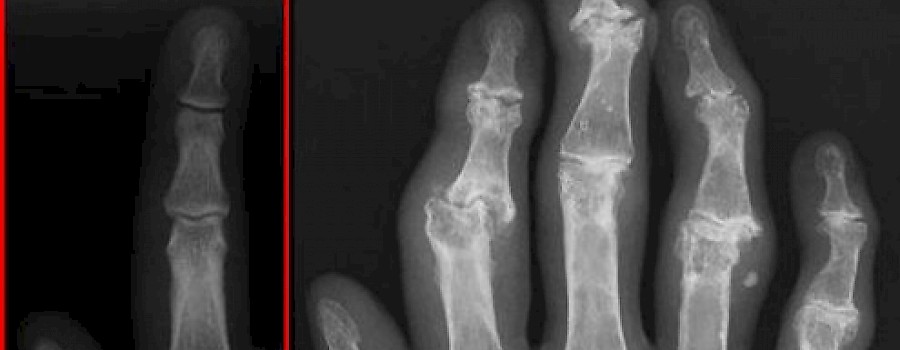

Arthrosezeichen

Arthrosezeichen sind die röntgenologisch sichtbaren Veränderungen, die typischerweise im Rahmen von degenerativen Gelenkerkrankungen (Arthrose) auftreten.